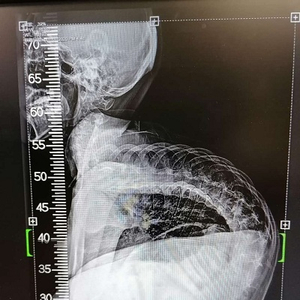

跑、跳这些最平常的动作,对于17岁的浙江大男孩小徐来说却是幻想,有时就连吃饭和呼吸都是一种奢侈。因患有罕见病脊髓性肌萎缩症,小徐脊椎严重弯曲,肌肉萎缩无力,大部分时间都只能躺在床上。即便如此,小徐一直没有放弃治疗,热爱生命的他用坚强的意志打动了很多人。

近日,小徐在上海交通大学医学院附属新华医院脊柱中心接受了脊柱矫形手术,穿上了“螺钉护甲”,身体外观和生命质量都大为改观,被疾病严重扭曲的身体一夜变直。小徐说,“命运对我虽然残酷,但我不会放弃任何希望,坚强生活。如果有余力的话,我还想帮助更多的人!”

长到17岁的小徐,身形弯曲,大部分时间都只能像蛇一样匍匐躺在床上,还常常呼吸困难,轻微的肺部感染就有发生呼吸衰竭的可能,甚至有生命危险。即便如此坎坷,但小徐始终不放弃求生的信念。

小徐因为神经肌肉萎缩,极重度侧弯,如果进行手术,术后极其容易出现呼吸衰竭。面对如此大风险的高难度手术,小徐的心肺功能是否能够耐受?术后会不会呼吸机拔管失败?

7月8日当天,新华医院杨军林教授的团队仅用了5个小时就完成了这样一例极重度的脊柱矫形手术,术中输血很少,一枚一枚的螺钉置入了身体中,犹如一件“螺钉护甲”,将小徐的脊椎托了起来,小徐蛇形的身体变直了。术后,小徐进入了监护室进行观察,各项生命体征都很平稳,当晚就拔除了气管插管进行自主呼吸了。专家透露,如果小徐恢复顺利,他身体外观和生命质量都将大为改观。